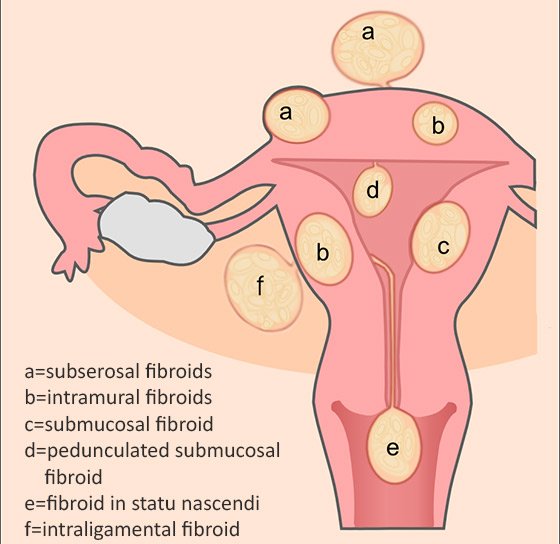

Types of Uterine Fibroids – Dr Pamela Tan | Uterine fibroids, Fibroids …

Types of Fibroid’s? | Fibroids, Hospital, Intramural

FIGO classification of uterine fibroids according to | Download …

Uterine fibroids. Fibroid types and uterine fibroids treatment | MED Expert